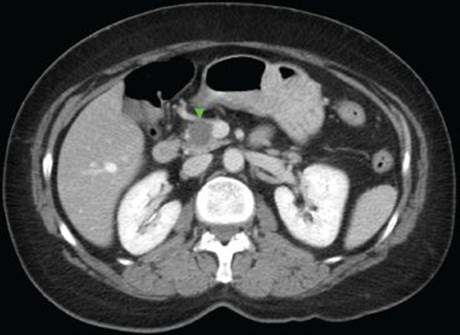

In our case, a pancreatic protocol CT scan including PO and IV contrast with 5-mm cuts demonstrated a dominant 3-cm tumor in the superiomedial aspect of the head of the pancreas abutting the superior mesenteric vein (Figure 1). The sensitivity of CT is directly related to the size of the tumor. Tumors >3 cm are detected in 83% to 95% of cases, tumor 1 to 3 cm are detected in 30% of cases, whereas tumors <1 cm are not detectable. Another limitation of CT scanning in the setting of gastrinoma is that only 50% of liver metastases are detected.

FIGURE 1 • Computed tomography scan demonstrating 3-cm gastrinoma at the head of the pancreas and abutting the superior mesenteric vein.